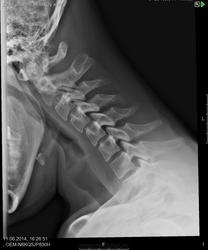

Пол пациента: Мужской пол Тип патологии: Метаболическое заболевание Область исследования: Скелетно-мышечная система Методы исследования: Rg Есть ли здесь функциональный блок сегментов C5-C6, C6-C7? https://radiomed.ru/sites/default/files/styles/case_slider_image/public/user/19785/m_c_spine_20140611_155947.jpg?itok=ohD7GSmA ID:38807 Ср, 11/06/2014 - 18:22 #1 Андрей Юрьевич Не на сайте Был на сайте: 2 недели 12 часов назад Зарегистрирован: 16.11.2008 - 22:16 Публикации: 18098 Блока нет. Блок - это когда нет движений, а тут они есть. Андрей Юрьевич Чт, 12/06/2014 - 11:13 #2 И.Бондаренко Не на сайте Был на сайте: 2 дня 6 часов назад Зарегистрирован: 13.09.2011 - 22:55 Публикации: 9206 Признаков нестабильности нет.

Блока нет. Блок - это когда нет движений, а тут они есть.

Признаков нестабильности нет.